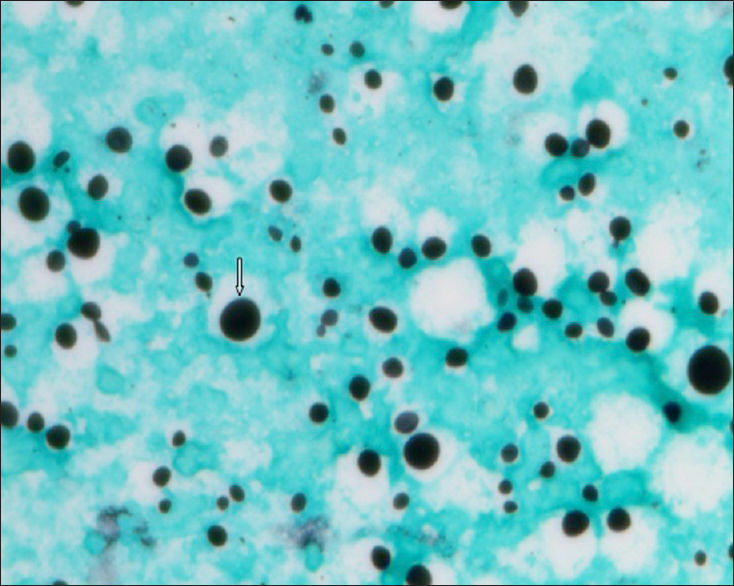

Coloração usada no exame direto Tinta nanquim

Coloração usada na Biópsia gomori- grocott